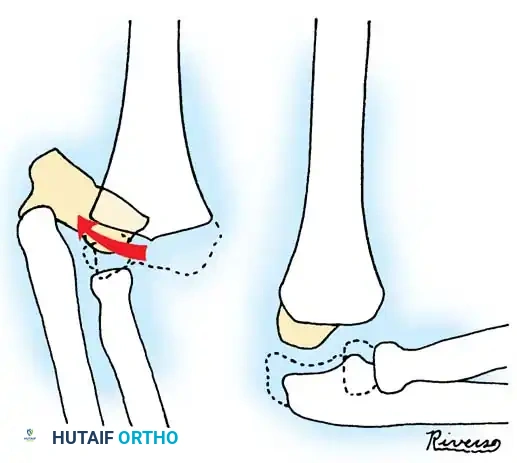

ADVANCED RECONSTRUCTION: ULNAR OSTEOTOMY FOR CHRONIC DISLOCATIONS

In cases of chronic radial head dislocation (often missed acutely or associated with plastic deformation of the ulna), simple open reduction is insufficient. The Hirayama Technique utilizes an ulnar osteotomy to overcorrect the angular deformity, thereby pulling the radial head back into the joint via the interosseous membrane.

TECHNIQUE 33-5: Osteotomy of the Ulna (Hirayama et al.)

- Preparation: Inflate a pneumatic tourniquet. Make a posterolateral skin incision exposing the radiohumeral joint and proximal third of the ulna. Excise intra-articular scar tissue.

- Osteotomy: Perform a subperiosteal osteotomy of the ulna 5 cm distal to the olecranon.

- Distraction and Angulation: Distract the osteotomy by 1 cm to lengthen the ulna.

- For Anterior Dislocation: Correct by posterior angulation of the ulna.

- For Lateral Dislocation: Correct by medial angulation of the ulna.

- Fixation: Secure the osteotomy with a metal plate bent to approximately 15 degrees. Ensure the radial head rests perfectly within the radial notch of the ulna without excessive radiocapitellar pressure.

- Closure: Approximate the anconeus. Do not repair the annular ligament, as this can restrict rotation.

- Postoperative Care: Apply a plaster splint in 90 degrees of flexion and full supination for 4 weeks, followed by aggressive active range of motion.

Fig. 33-36 Overcorrection with posterior convexity for anterior dislocation.

Fig. 33-37 Overcorrection with medial convexity for lateral dislocation.